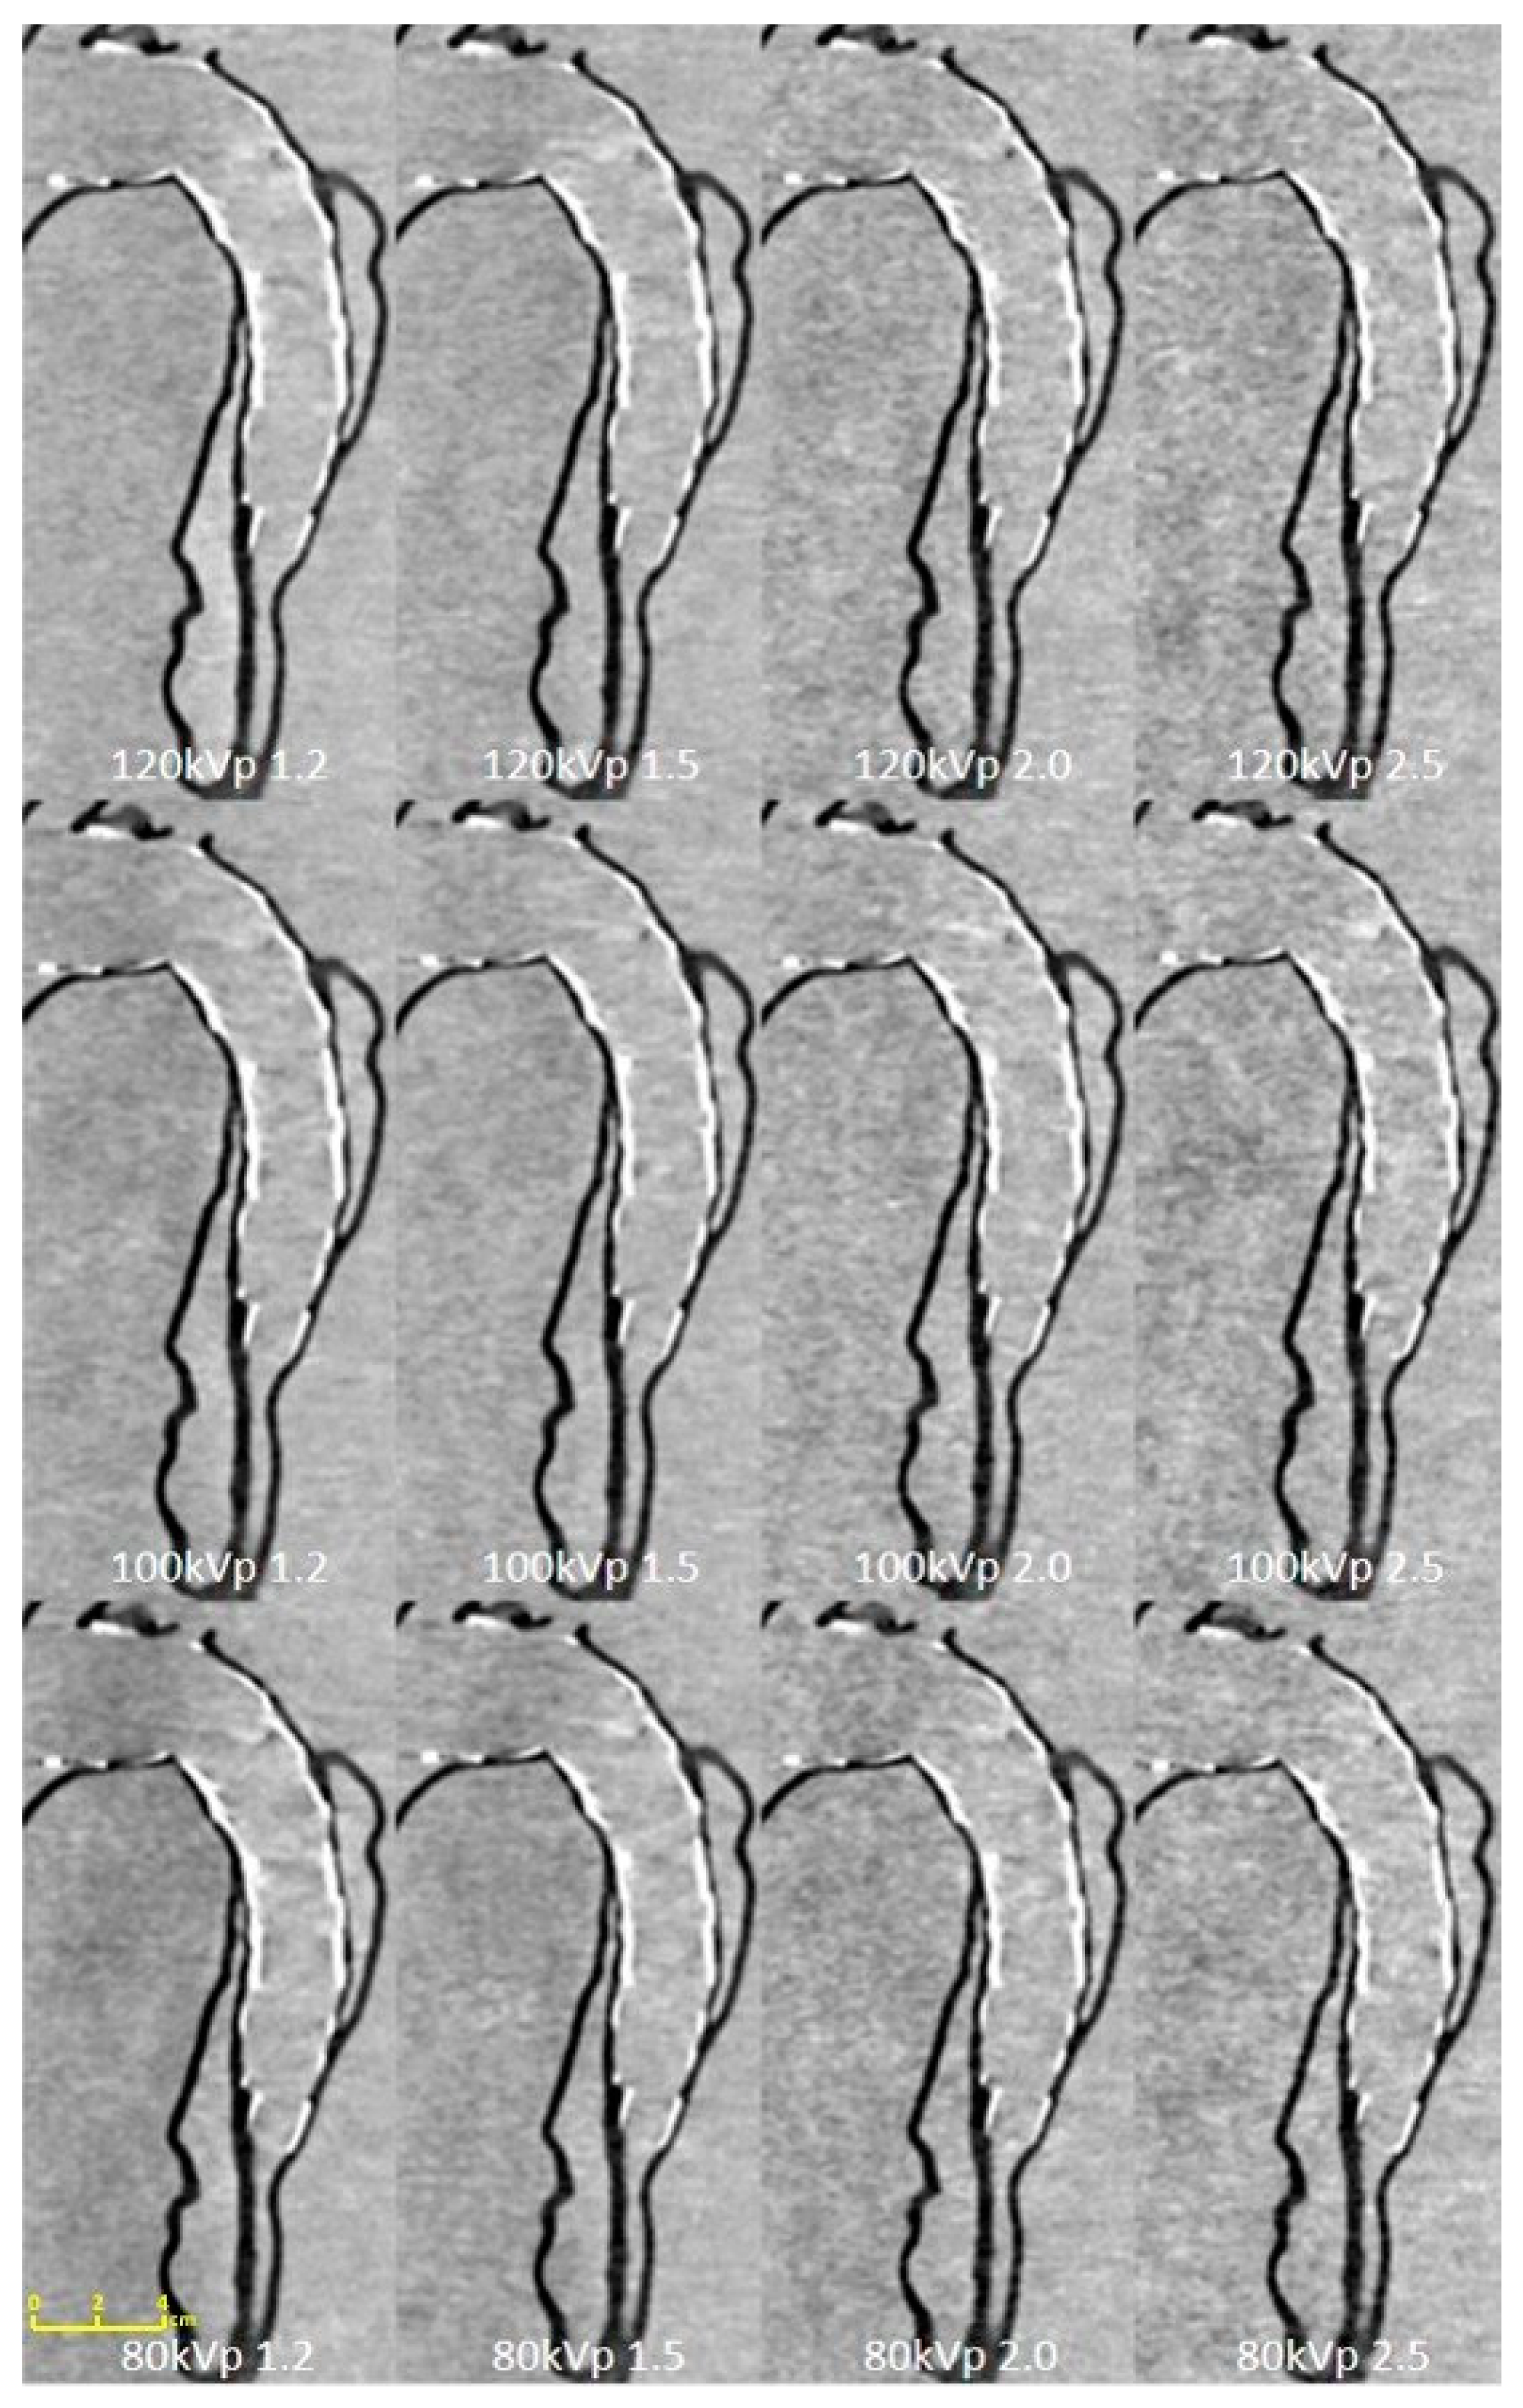

2.4. Aortic CTA Scanning Protocols

2.5. Quantitative Assessment of Image Quality

| Tube Voltage | 80 kVp | 100 kVp | 120 kVp | |||||||||

|---|---|---|---|---|---|---|---|---|---|---|---|---|

| Pitch Value | 1.2 | 1.5 | 2.0 | 2.5 | 1.2 | 1.5 | 2.0 | 2.5 | 1.2 | 1.5 | 2.0 | 2.5 |

| True lumen of proximal descending aorta | 23.93 ± 9.34 | 20.30 ± 1.69 | 19.64 ± 1.03 | 13.70 ± 1.42 | 27.60 ± 1.47 | 22.19 ± 2.14 | 19.14 ± 3.75 | 12.60 ± 0.38 | 25.64 ± 4.69 | 25.10 ± 2.74 | 19.93 ± 0.67 | 19.23 ± 3.74 |

| False lumen of proximal descending aorta | 24.70 ± 10.66 | 23.40 ± 0.90 | 20.86 ± 1.98 | 21.34 ± 2.08 | 24.18 ± 2.86 | 23.82 ± 0.64 | 16.63 ± 3.31 | 17.04 ± 1.24 | 26.18 ± 2.44 | 27.61 ± 3.93 | 22.06 ± 1.51 | 24.00 ± 2.94 |

| True lumen of middle descending aorta | 25.29 ± 7.43 | 25.10 ± 3.58 | 18.66 ± 1.19 | 16.62 ± 1.28 | 25.65 ± 2.16 | 25.91 ± 0.29 | 14.74 ± 0.58 | 18.40 ± 1.92 | 23.68 ± 2.33 | 26.21 ± 0.26 | 20.61 ± 1.24 | 19.81 ± 1.04 |

| False lumen of middle descending aorta | 18.12 ± 2.80 | 22.13 ± 1.54 | 10.11 ± 0.60 | 12.47 ± 0.54 | 20.86 ± 2.23 | 26.27 ± 3.77 | 15.62 ± 0.77 | 12.16 ± 1.16 | 20.15 ± 1.29 | 29.91 ± 4.84 | 14.03 ± 0.80 | 13.53 ± 0.51 |

| CTDIvol (mGy) | 0.07 | 0.08 | 0.06 | 0.06 | 0.1 | 0.1 | 0.08 | 0.07 | 0.11 | 0.1 | 0.08 | 0.07 |

| DLP (mGy/cm) | 2.8 | 2.9 | 2.2 | 2.1 | 3.9 | 3.8 | 2.7 | 2.4 | 4.1 | 3.8 | 2.8 | 2.5 |

| Effective dose (mSv) | 0.04 | 0.04 | 0.03 | 0.03 | 0.05 | 0.05 | 0.04 | 0.03 | 0.06 | 0.05 | 0.04 | 0.04 |